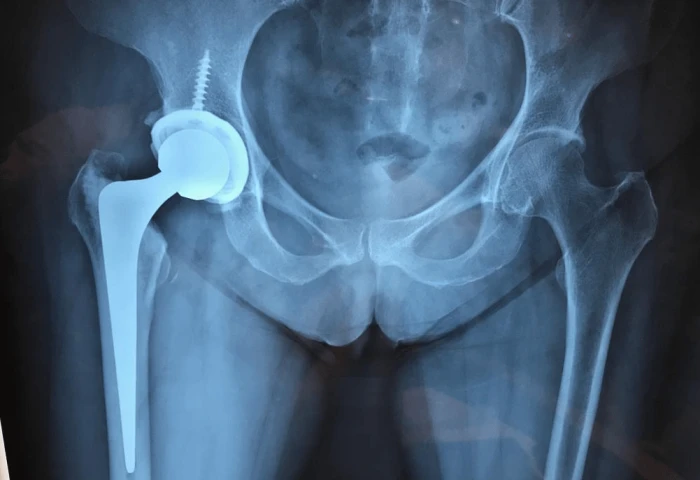

Procedimento indicado para artrose avançada, proporcionando alívio da dor e recuperação da mobilidade.